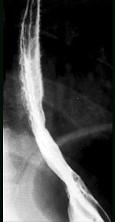

问题 男,34岁,胸骨后烧灼痛1周,伴吞咽痛,餐后平卧时加剧,食管钡餐检查如图,应诊断为 ( )

选项 A.食管癌 B.贲门失弛缓症 C.反流性食管炎 D.食管静脉曲胀 E.正常食管表现

答案 C